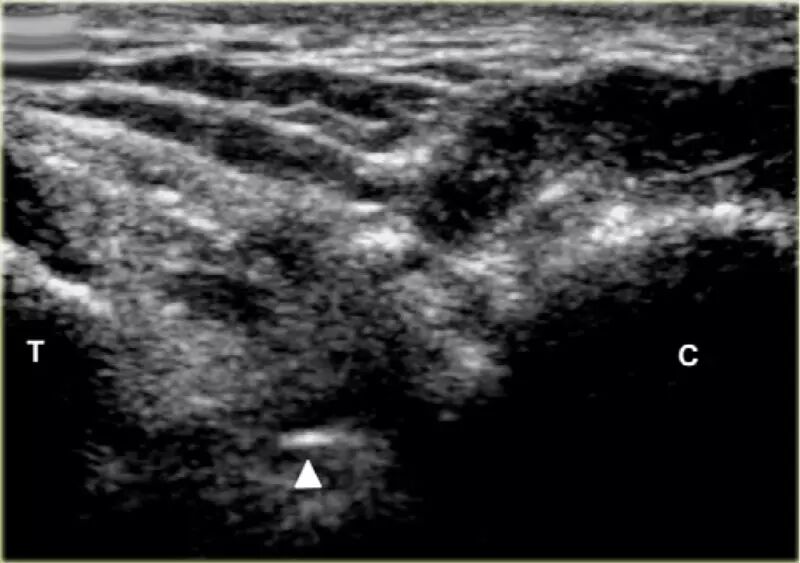

在跗骨窦被识别为跟骨的前处理和距骨颈之间的三角空间。针(箭头)的前端的锥形跗骨窦,这是由距骨(T)和跟骨(C)的边界内可以看到。

根据炎症的程度,可能存在空间的充血,并且可能存在中间血管可见,这是人们希望避免的。但是这又是比较容易的,特别是彩色多普勒。